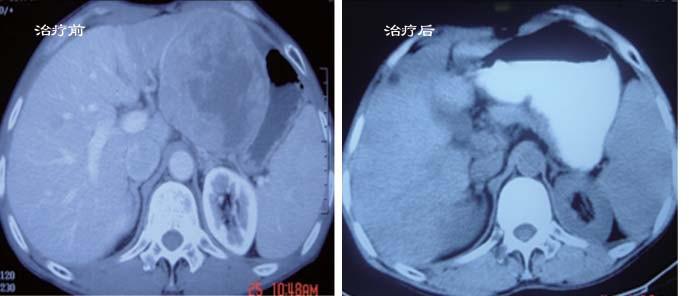

肝癌并肝内多发转移,患者治疗前后对比

CT( 首都医科大学附属复兴医院):肝左外叶巨大肿物,最大截面约 9.3 cm×10 cm, 分叶状,部分边界不清,突出于肝脏轮廓之外,贴邻推压心包、胃体、贲门、胰腺及腹腔动脉干。动脉期肿物呈不均匀强化,部分高于周围肝组织。门脉期密度减低,低于周围肝组织。动脉期肝右前叶及左内叶见多发高密度结节灶,最大者约 2.1 cm×2.8 cm, 门脉期密度减低。余肝右叶见多发小低密度灶,最大者约 1.3 cm×1.5 cm,动脉期部分呈低密度,部分显示不具体,门脉期均呈低密度。

入院后行肝左叶肿瘤缓释库治疗 3 次。于 2004 年 5 月 28 日复查 B 超示肝左外叶肿瘤缩小至 7.8 cm×6.5 cm,并行此肿块缓释库治疗 1 次。

于 2005 年 5 月 8 日复查 B 超示肝左外叶肿瘤缩小至 3.5 cm×3.4 cm,并行此肿块缓释库治疗 1 次,且肝内其他散在病灶消失。患者治疗前后对比见图 8-3。